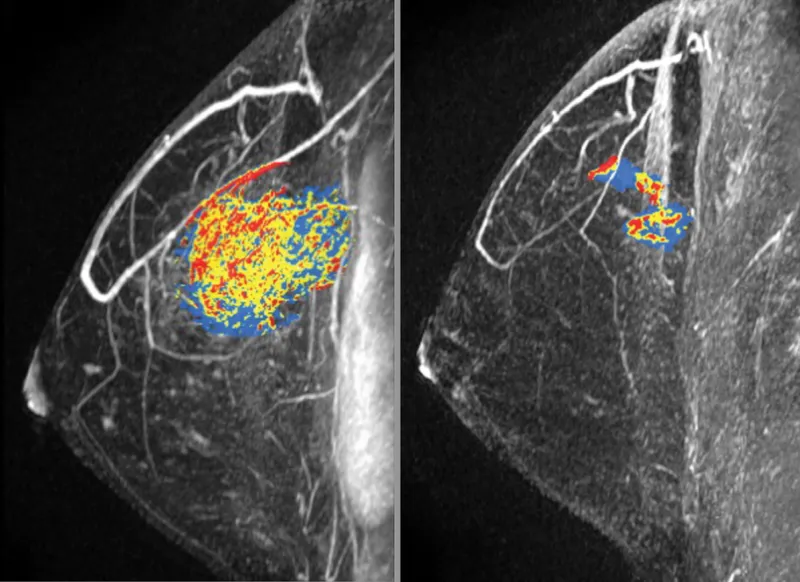

- MRI:

- New enhancing mass (Type II/III kinetics).

- New non-mass enhancement (NME) (segmental/ductal).

- MRI has the highest sensitivity for detecting local recurrence, especially in dense breasts.